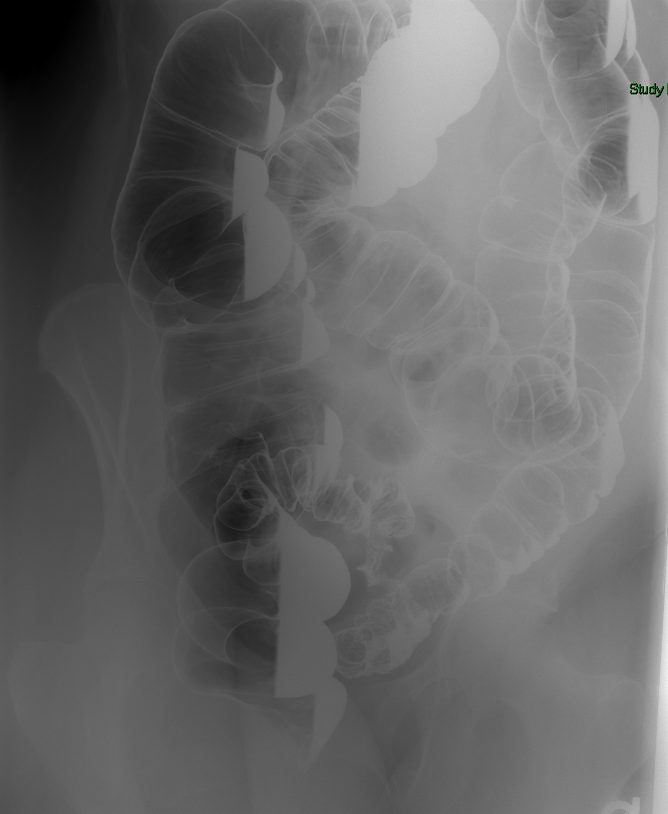

- The technologist will obtain a scout image. Assess the image for any possible contraindications such as pneumoperitoneum, evidence of ileus or obstruction, or residual contrast material

(key image 1).

- Once 15 minutes has passed since the patient drank the barium, the technologist will obtain a prone (if possible) radiograph

(key image 2).

- The technologist will obtain radiographs at 30, 45, and 60 minutes after the initial administration of barium. If the column of contrast material has not reached the large bowel on the 60 minute film, the technologist will obtain images every 30 minutes until contrast can been seen in the cecum

(key image 3)

(key image 4)

(key image 5).

- The technologist will have you review every image.

- Obtain images of the terminal ileum and the ileocecal valve filled with contrast material

(key image 6)

(key image 7)

(key image 8)

(key image 9)

(key image 10).

- Obtain spot images of the remainder of the small bowel

(key image 11)

(key image 12)

(key image 13)

(key image 14).

- Obtain images of all four quadrants. Use the compression paddle to separate loops of small bowel from each other.